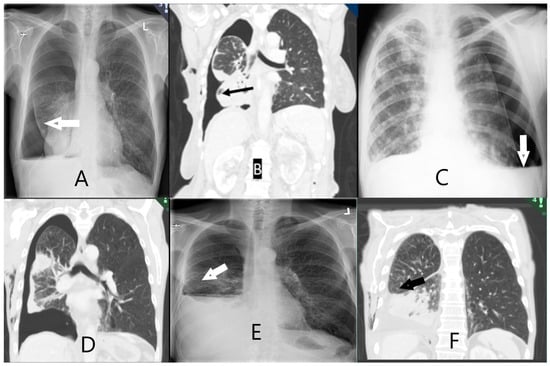

2.7. Scoring of Non-Expandable Lung (NEL)—Reference Standard

As per the method described by Salamonsen et al. [20], NEL was defined based on a combination of clinical observations and post-thoracentesis radiology (Table A3). Two interventional pulmonologists (AS and JS) independently assessed the study data after four months of follow-up. Post-thoracentesis radiology reports and images obtained both directly following thoracentesis and in the follow-up period were available, and assessors recorded whether they observed air (or hydropneumothorax) in the pleural space surrounding the lower lobe, with examples shown in Figure 2. The assessors were blinded to the results from the index tests, e.g., SWE, M-mode, and B-mode measurements. The outcome was classified as: NEL (definite NEL, probable NEL), expandable lung (EL) (probably expandable, definitely expandable), or “Unable to score”. In the event of disagreeing diagnoses between assessors, a third interventional pulmonologist (UB) assessed the study information and a consensus was achieved. All assessments were made while blinded to the other assessor’s results. The assessors were provided with clinical observations during thoracentesis: development of chest tightness or severe coughing not alleviated by thoracentesis pause, air in chest tube, or undrainable pleural effusion despite unblocked chest tube.

Figure 2. Radiological images of non-expandable lung (NEL). CXR (image (A,C,E)) and CT-scan (image (B,D,F)). (A) NEL. Lower lobe with thickened visceral lining. (B) NEL. Obstructive tumour of the lower lobe. (C) NEL. Hydropneumothorax following thoracentesis. (D) NEL with thickened pleura. (E) NEL. Small hydropneumothorax following thoracentesis. (F) NEL. Pleural effusion following thoracentesis. Fluid has replaced initial air in the pleural space seen on CXR after thoracentesis.